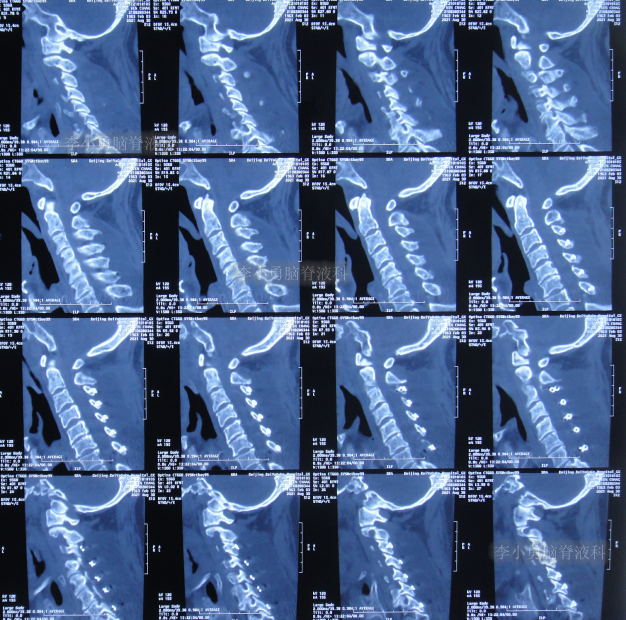

2021年8月30日(入院第2天),术前查颈椎影像示未见明显异常(图-5);进行了脑室外引流术(图-6)。

图-5:2021年8月30日颈椎影像